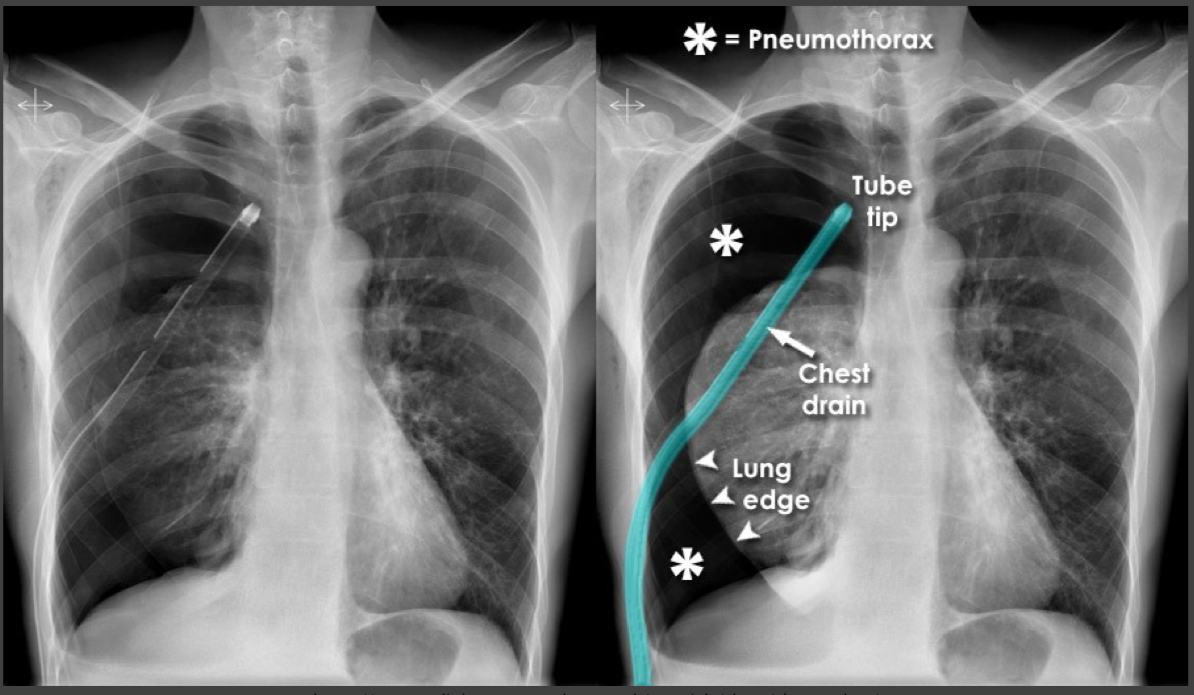

Pneumothorax

No lung markings.

Mediastinal shift with tracheal deviation.

Depressed left hemidiaphragm.

Treatment: chest tube insertion (note number of holes in tube).